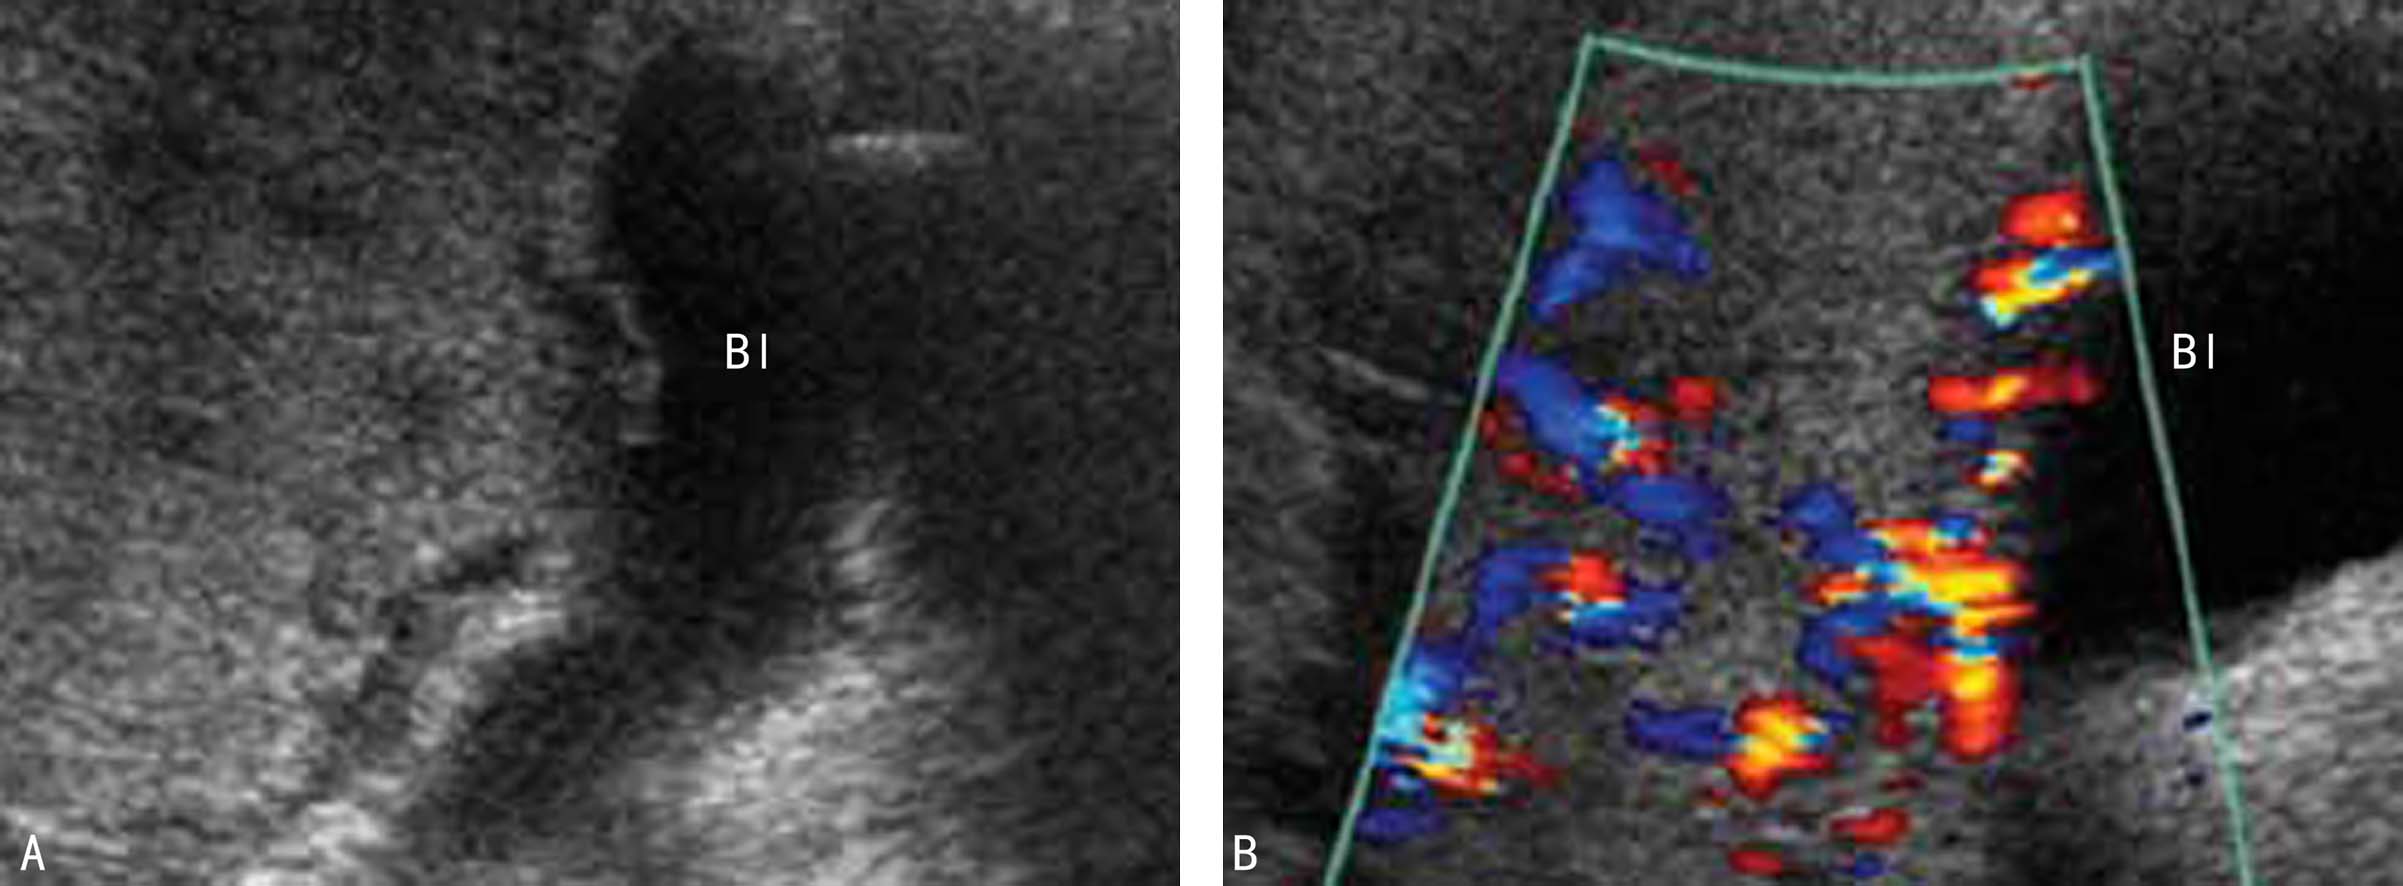

2D-US可以采取TAU或结合使用TVU、TSU检查VP。在宫颈内口上方显示数个或多个圆形无回声及血管(图1A),CDFI显示不同于子宫动脉血流的胎儿动脉低阻力血流(图1B)时应当考虑VP。胎盘的显示及脐带附着部位的检查有助于VP诊断,如果发现帆状脐带附着、分叶胎盘、多叶胎盘等,结合阴道大量流出新鲜血液则强烈支持VP的诊断。需要注意的是二维超声显像检查可能没有任何异常发现,对于需要排除或可疑VP的病例,使用多普勒能量图或CDFI检查,如果在宫颈内口处显示或寡或多的动脉和(或)静脉血流即应做出VP的诊断。少量的出血、在宫颈内口处形成血肿可影响前置血管的显示,反复多次2D-US或在血肿吸收以后有可能发现前置血管。

图1血管前置